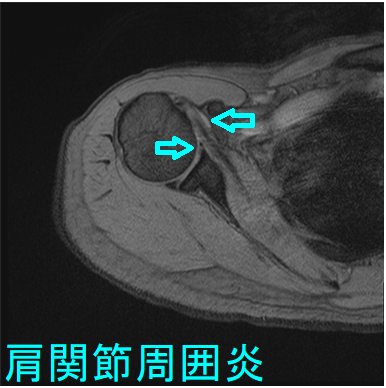

肩関節周囲炎とは肩・肩周囲の炎症で、中年に起こり易いため五十肩と呼ばれます。初期には肩関節を動かしても動かさなくても痛み、特に夜間の痛みが強くなります。数か月-数年で、肩関節を動かしにくくなり、服を着替えるにも困難が生じます。

五十肩は学術的な病名ではなく、国際的には癒着性関節包炎(adhesive capsulitis)や凍結肩(frozen shoulder)と呼ばれます。

肩関節周囲炎(癒着性関節包炎・凍結肩)は、糖尿病や甲状腺疾患との関連が強い[Am Fam Physician. 2008 Feb 15;77(4):453-60.]。

糖尿病の10%から20%に五十肩(肩関節周囲炎・凍結肩・癒着性関節包炎)が発病するとされますが、その原因は不明です。甲状腺ホルモンは、骨、軟骨、腱に影響するため、甲状腺機能低下症・甲状腺機能亢進症も、五十肩の発病に関連あるとされます。(J Biol Regul Homeost Agents. 2016 Jul-Sep;30(3):867-870.)(Arthritis Rheum. 1987 Aug;30(8):936-9.)

甲状腺機能低下症の重症度と、五十肩(肩関節周囲炎・凍結肩・癒着性関節包炎)の重症度に相関が認められます。(J Shoulder Elbow Surg. 2017 Jan;26(1):49-55.)